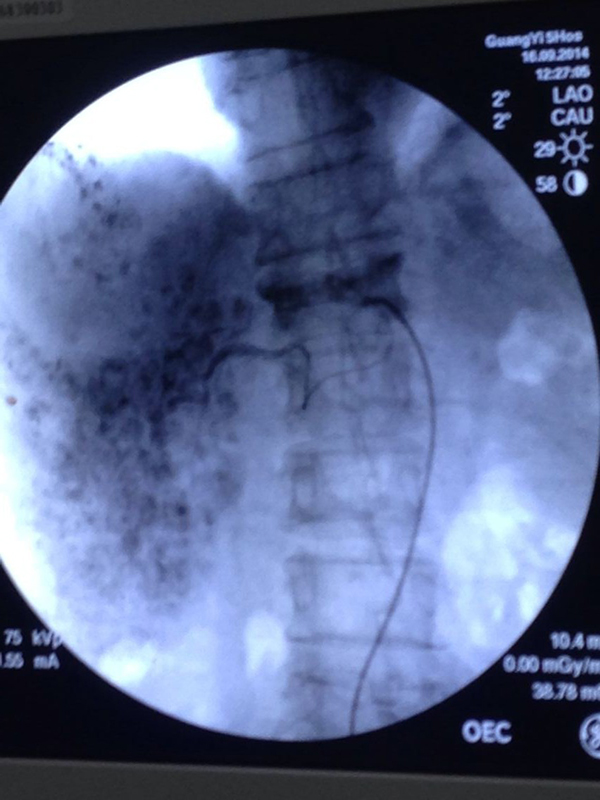

院内率先开展肝癌经皮肝动脉灌注化疗及栓塞、食管癌支架植入、梗阻性黄疸支架植入解除梗阻性黄疸、微创介入治疗子宫内膜癌、宫颈癌、肺癌等,开展输液港解决化疗管道输送方式,尤其是与麻醉科联合开展儿童输液港植入、经皮肺肿物及肝脏肿物穿刺活检,甲状腺结节穿刺活检等;

开展的经皮肝动脉灌注化疗及栓塞术、食管支架植入术、胆道支架植入术、经皮选择行动脉栓塞术治疗子宫肌瘤、子宫颈癌等妇科肿瘤、输液港植入术、经皮各种穿刺活检术等已经逐步与国内的先进水平接轨;

肝癌经皮肝动脉化疗栓塞术